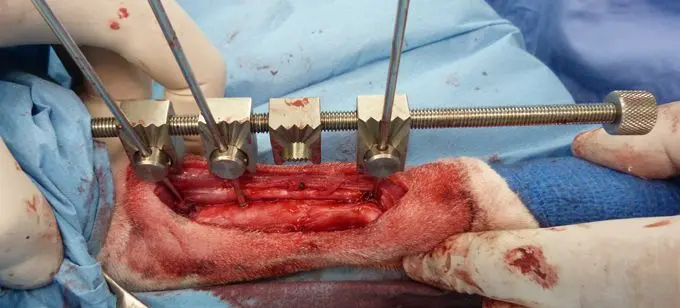

Para la colocación de las agujas, podemos utilizar los cilindros como guías de broca, tarotar y posteriormente introducir la aguja de forma retrógrada en el cilindro correspondiente, insertar éste en el orificio de la rótula y roscar la aguja en el hueso. (Vease vídeo). Finalmente procedemos a la osteotomía del cúbito y radio. Iniciaremos la elongación tras un periodo de latencia (sin distracción) de 3-5 días. Cada día el propietario debe girar HACIA LA IZDA, la barra de distracción media vuelta (equivalente a 1.0 mm). En su parte distal enroscamos una arandela grafilada para facilitar el giro.

Aspecto final del paciente con el elongador “in situ”. Debe planificarse cuidadosamente que disponemos del suficiente espacio en la barra distractora proximal y distal que nos permita la elongación a realizar. La barra proximal puede cortarse con una cizalla si es excesivamente larga y se clava en la piel del paciente. La parte distal no debería cortarse ya que en caso de hacerlo, dificulta la inserción de la arandela grafilada. No debe sobrepasar el nivel de la articulación metacarpo-falangiana